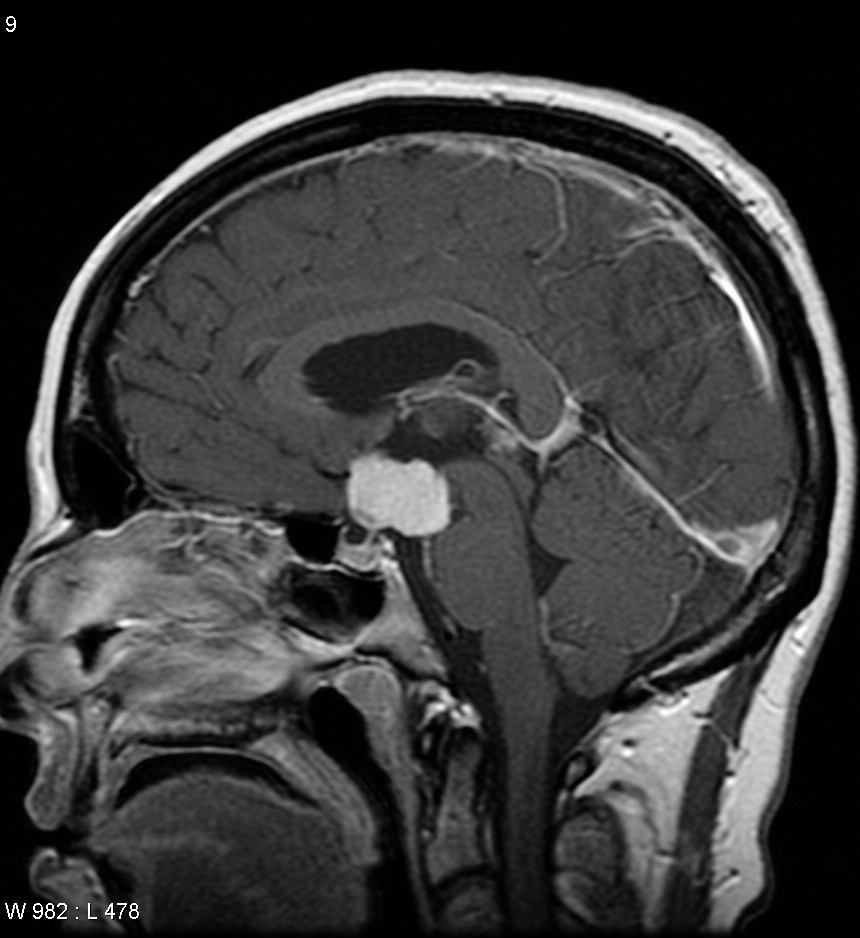

Το κρανιοφαρυγγίωμα, ICD-10 D44.4 είναι ένας τύπος εγκεφαλικού όγκου που προέρχεται από τον εμβρυϊκό ιστό της υπόφυσης και εμφανίζεται πιο συχνά σε παιδιά, αλλά και σε άνδρες και γυναίκες στα 50 και τα 60 τους.

Το κρανιοφαρυγγίωμα είναι ένα σπάνιο, συνήθως υπερεφιππιακό νεόπλασμα, το οποίο μπορεί να είναι κυστικό και αναπτύσσεται από τις φωλιές του επιθηλίου που προέρχονται από τη θήκη του Rathke. Ο θύλακας Rathke είναι ο εμβρυακός πρόδρομος της πρόσθιας υπόφυσης.

Τα κρανιοφαρυγγιώματα είναι, συνήθως, πολύ αργά αναπτυσσόμενοι όγκοι. Προκύπτουν από τα κύτταρα κατά μήκος του μίσχου της υπόφυσης, συγκεκριμένα από τις φωλιές του οδοντογενούς επιθηλίου εντός της υπερεφιππιακής και διεγκεφαλικής περιοχής και, ως εκ τούτου μπορεί να περιέχουν εναποθέσεις ασβεστίου η να περιβάλλονται από ασβέστιο και είναι εμφανείς σε μια ακτινογραφία.

Με την αξονική και την μαγνητική τομογραφία αποτελούν αρκετά συχνό εύρημα (11-22%). Υπάρχουν ενδοκρινικές διαταραχές λόγω επηρεασμού της υπόφυσης. Η κορτιζόλη π.χ. θα μειωθεί λόγω των επιπτώσεων στην παραγωγή ACTH.

Συχνότερα εντοπίζονται εντός του τουρκικού εφιππίου. Είναι δυνατόν όμως να εντοπιστούν και να επεκταθούν και στην υπεριφιππιακή δεξαμενή.